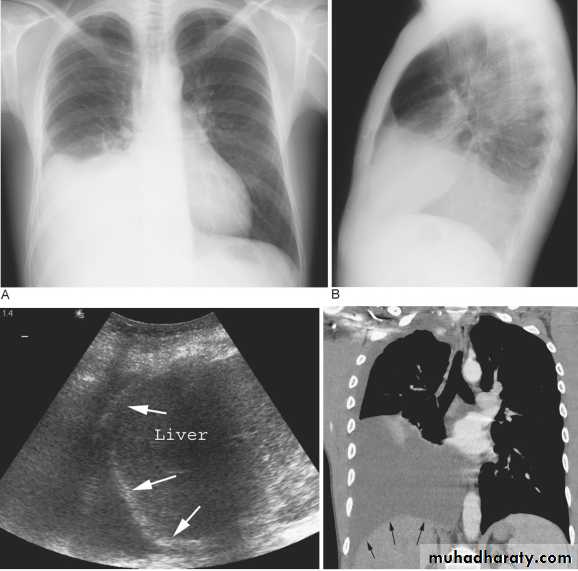

Pleural Effusion on Chest Radiographs.

Posteroanterior (A) and lateral (B) chest radiographs demonstrate the typical meniscoid appearance (arrows) in a patient with a left pleural effusion

Hydropneumothorax.

When fluid and air are present in the pleural space on an upright chest x-ray, a perfectly straight horizontal line will extend all the way from the spine to the edge of the pleural cavity. In this patient, a loculated right basilar hydropneumothorax is present.

The air/fluid interface is easily seen (arrows). If this were a lung abscess, the air/fluid level would be very unlikely to extend all the way from the medial to the lateral aspect of the hemithorax.

Massive pleural effusion with mediastinal shift to the left.

(A) Chest radiograph

(B) CT coronal reconstruction. A massive effusion displaces the mediastinum to the left. CT shows the important pleural effusion together with the enhanced atelectatic left lung.

Note also the depression of the right hemidiaphragm (arrows).

chest practice

Subpulmonary pleural effusion. On the (A) erect PA and (B) lateral radiograph the effusion simulates a high hemidiaphragm. (C) Ultrasound and (D) CT clearly show that the effusion is located above the diaphragm. Arrows = diaphragmatic area.